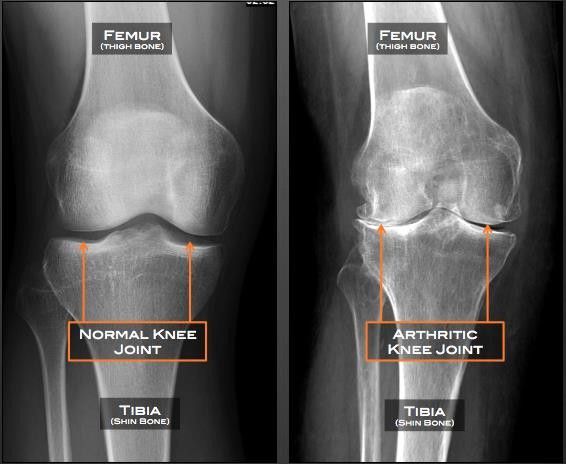

Lutut yang normal dan yang mengalami osteoarthritis (orthobullets.com)